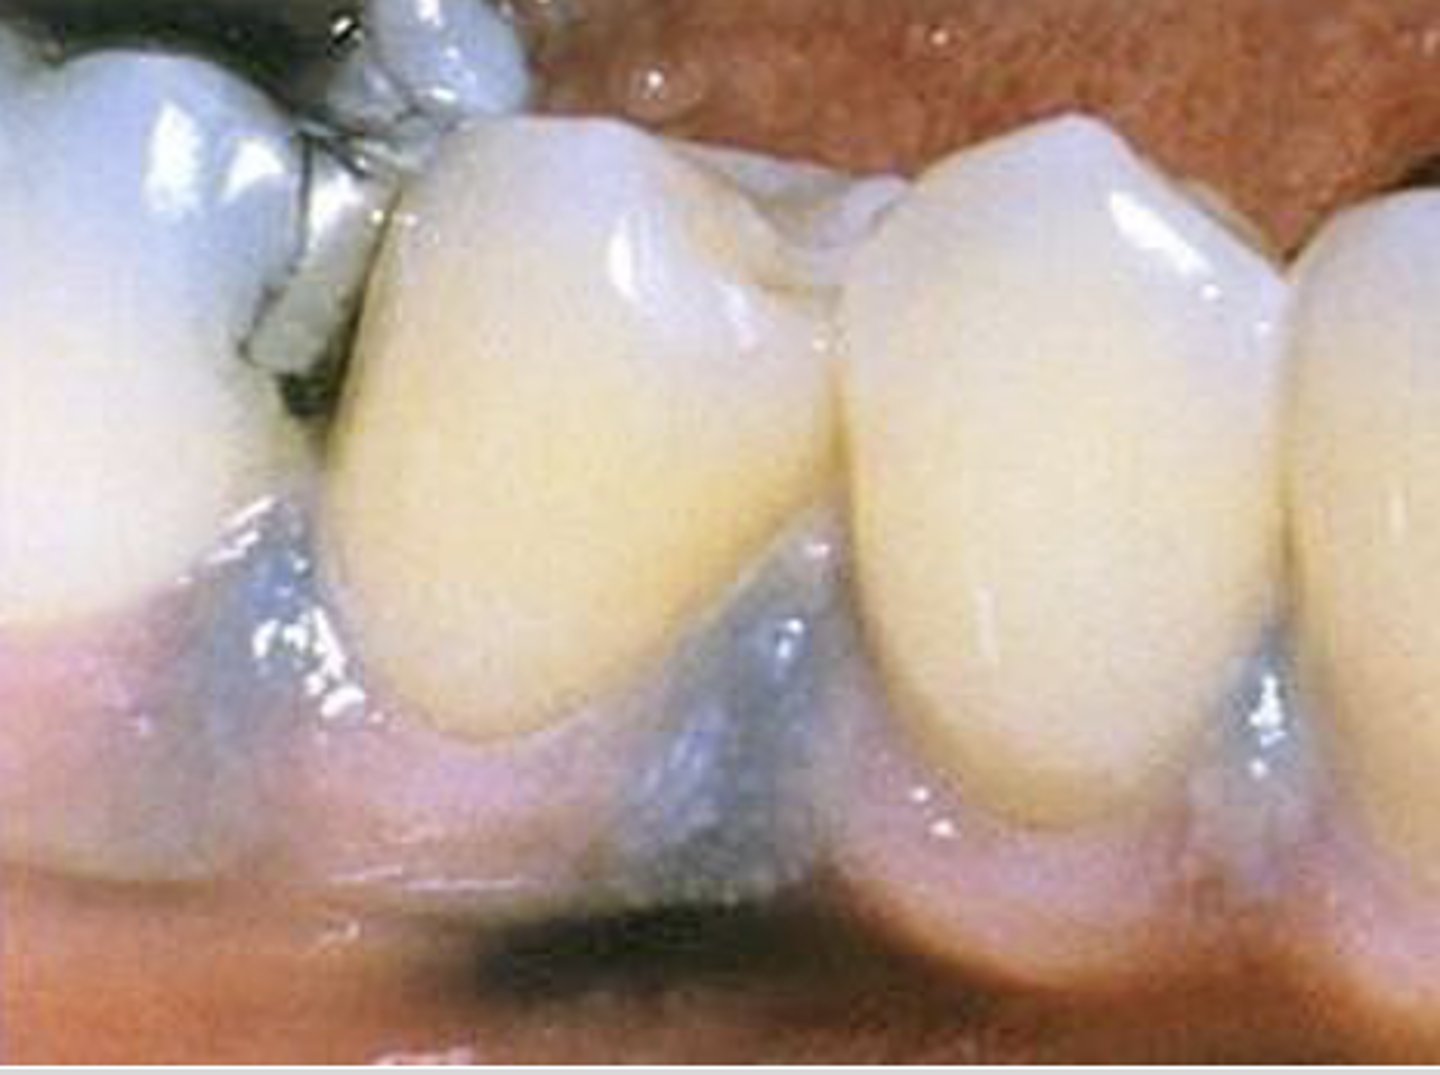

What type of pigmented lesion?

amalgam tattoo

These are histopathologic features of what?

- Pigmented fragments

- Staining of reticulin fibers

- Large fragments surrounded by fibrosis

amalgam tattoos